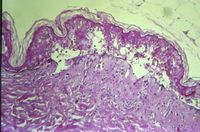

Histopathology of SJS/TEN

From the personal collection of Dr A. Kowal-Vern